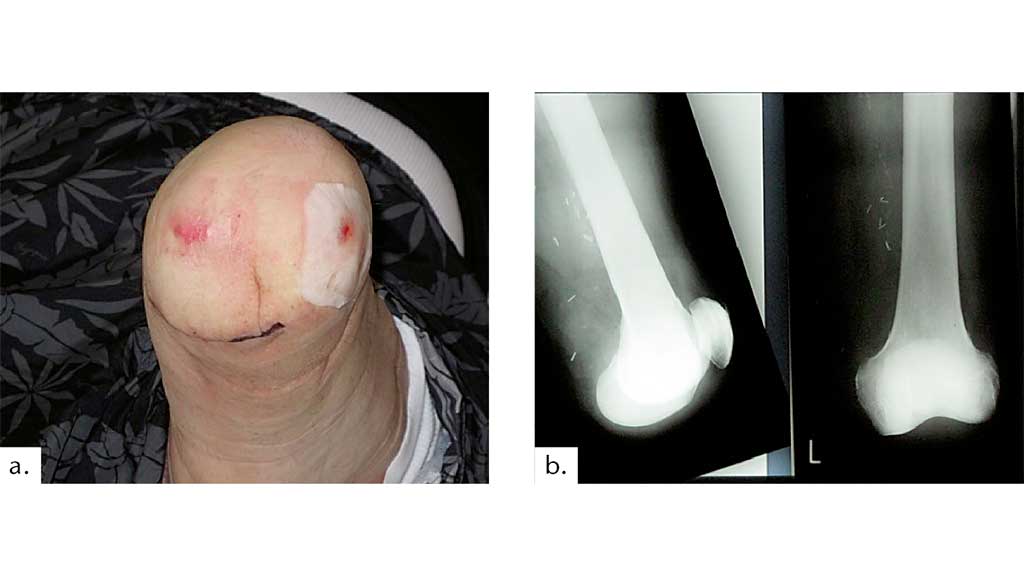

Druckstellen, die während des Gebrauchs der Knieexartikulationsprothese über der Patella und über dem lateralen und medialen Femurkondylus bei primär korrekter Hautnaht außerhalb der Belastungszone und regelhafter Wundheilung entstehen, zwingen den Amputierten immer wieder, seine gewohnten Aktivitäten des täglichen Lebens einzuschränken (Abb. 11).